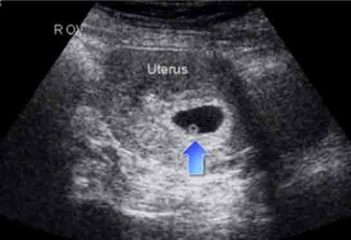

23 haftalık gebelik, hamileliğin ikinci trimesterinin sonlarına yaklaşıldığı bir dönemi ifade eder. Bu süre zarfında, hem anne hem de bebek için birçok önemli gelişim ve değişiklik yaşanmaktadır. Bu makalede, 23 haftalık gebelik dönemindeki fiziksel ve duygusal değişimlerin yanı sıra, bebeğin gelişimi, anne adayının sağlığı ve dikkat edilmesi gereken hususlar ele alınacaktır. Bebeğin Gelişimi23 haftalık gebelikte bebek, hızla büyümeye devam etmekte ve birçok önemli gelişim sürecinden geçmektedir. Bu dönemde, bebeğin gelişimiyle ilgili bazı önemli noktalar şunlardır: